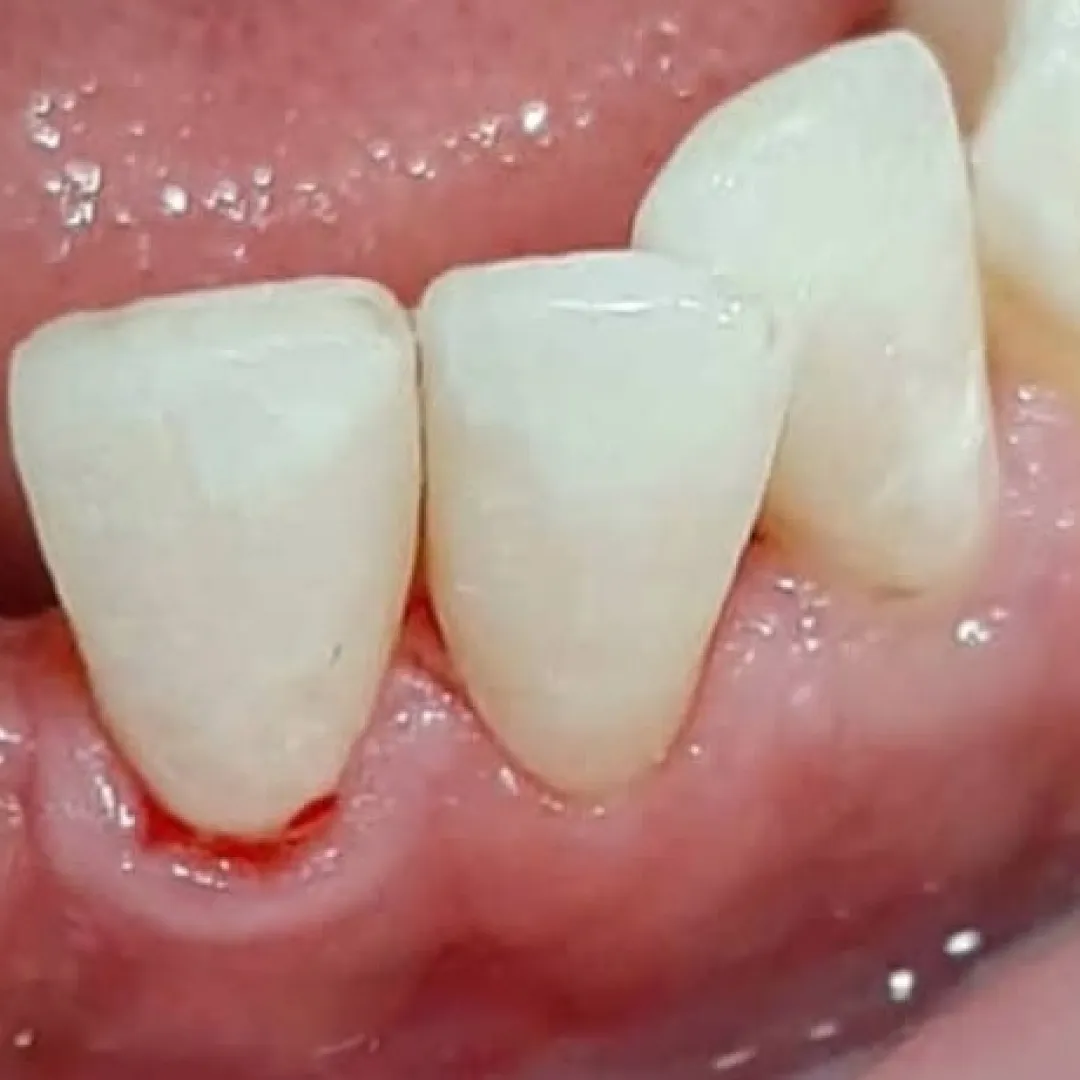

Восстановление коронковой части зуба временным пломбировочным материаломСмотреть работуСрок лечения:90 минутСумма лечения:14 300 руб.